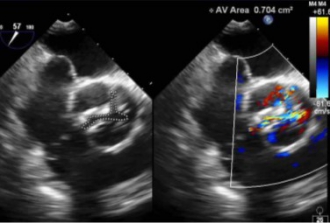

心エコー

大動脈弁狭窄症は、弁口面積や通過血流速度などの精密な計測が必須です。最初に、経胸壁心エコー検査を行い重症度を判定します。

手術中の経食道心エコーにより、合併症発生がないかモニタリングを常に行い、大動脈弁と周囲の詳細な評価をすることで、重篤なトラブルを回避し最小限にすることを目標に取組んでいます。

手術中の経食道心エコーにより、合併症発生がないかモニタリングを常に行い、大動脈弁と周囲の詳細な評価をすることで、重篤なトラブルを回避し最小限にすることを目標に取組んでいます。

3Dエコーにより、手術中の解析から、適正なステントサイズ選択を検証したり、リアルタイムでの形態評価を行うことが可能です。